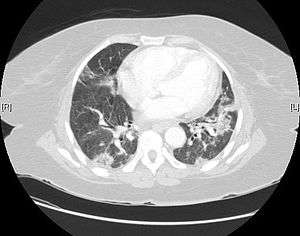

| Usual interstitial pneumonia seen on CT scan. Honeycomb fibrosis is seen at the bases of both lungs. | |

UIP may be diagnosed by a radiologist using computed tomography (CT) scan of the chest, or by a pathologist using tissue obtained by a lung biopsy. Radiologically, the main feature required for a confident diagnosis of UIP is honeycomb change in the periphery and the lower portions (bases) of the lungs.[2] The histologic hallmarks of UIP, as seen in lung tissue under a microscope by a pathologist, are interstitial fibrosis in a "patchwork pattern", honeycomb change and fibroblast foci (see images below).[3]